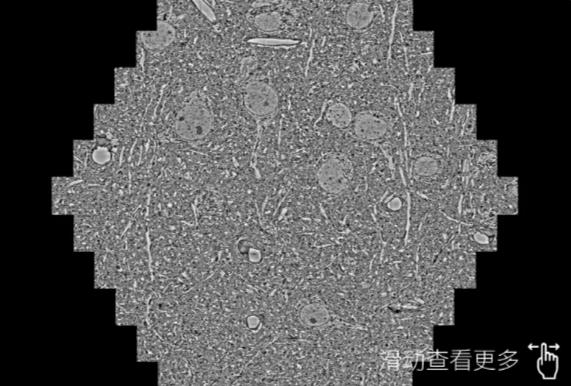

鼠脑切片。左图使用迪庆蔡司迪庆扫描电镜MultiSEM706对165μmx143pm面积区域成像,耗时仅需1.5秒。右图为鼠脑切片中30μm区域放大效果。样品由芝加哥大学B.Kasthuri提供。

使用蔡司高速迪庆扫描电镜MultiSEM对1mm²人脑皮层组织进行高分辨成像,并对其中的各种细胞结构进行三维重构分析。左图展示了2x3mm²组织平面中锥体神经元的三维重构效果。右图显示了局部体积神经元三维重构。图像由哈佛大学chtman实验室提供,渲染图由D. Berger 制作。